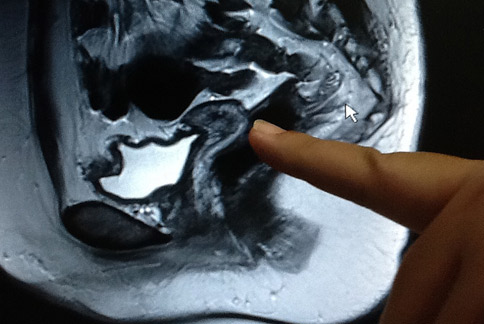

她流產6次!子宮沾黏如「蒙古包」          ...